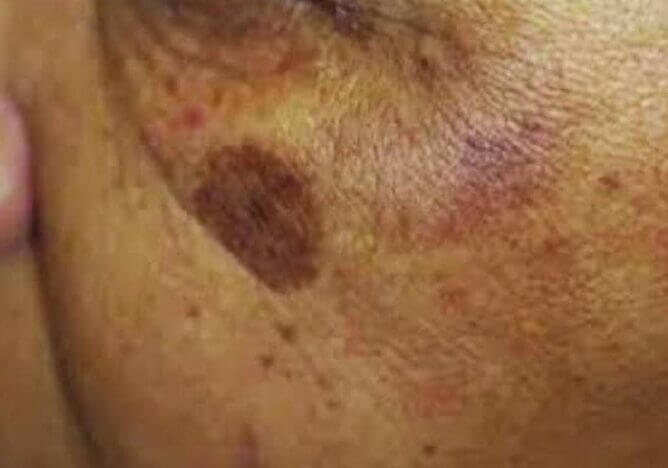

Dyschromia

Mottled Hyperpigmented Lesions/Patches

Common skin condition with unknown pathogenesis

Associated with solar and hormonallystimulated melanocytes (increasing melanocyte stimulation hormone, MSH) causing uneven increases in facial melanin.

More commonly found in races with higher pigmentation but can occur in all skin types.

How it works

- Induce keratinocyte turnover and “restore” the normal pigment activity of melanocytes in over pigmented areas.

- This occurs at the dermal-epidermal junction (DEJ).

- This DEJ-shallow dermis area is the target depth to microneedle.

Pigmentation Conditions

Solar lentigines occur due to excessive production of melanin pigment which results from overexposure to UV rays from the sunlight or tanning beds

How it works

- Induce keratinocyte turnover and “restore” the normal pigment activity of melanocytes in over pigmented areas.

- This occurs at the dermal-epidermal junction (DEJ).

- This DEJ-shallow dermis area is the target depth to microneedle.